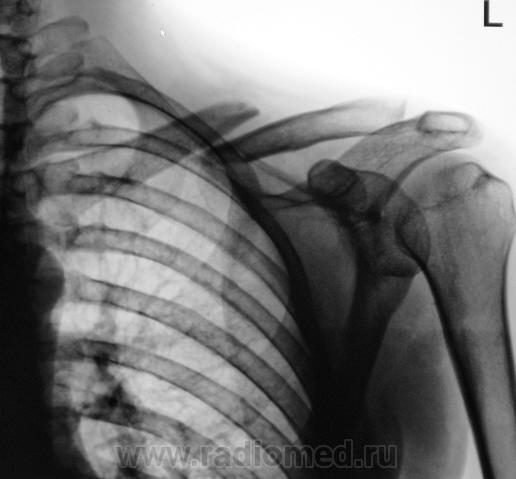

Пол пациента: Мужской пол Тип патологии: Травма Область исследования: Скелетно-мышечная система Методы исследования: Rg Травма. Рентгенограмма ключицы в день травмы и контроль через 7 дней. Контроль через 7 дней. https://radiomed.ru/sites/default/files/styles/case_slider_image/public/user/12/2.p1270023.jpg?itok=nwmIMaFT https://radiomed.ru/sites/default/files/styles/case_slider_image/public/user/12/3.p1270023a.jpg?itok=i7xHWQwq ID:11560 Чт, 27/01/2011 - 18:19 #1 Александр Викторович Не на сайте Был на сайте: 8 лет 3 месяцев назад Зарегистрирован: 31.07.2010 - 13:05 Публикации: 639 в таком положении если срастется, то и не плохо, тем более с апликациями гвоздями